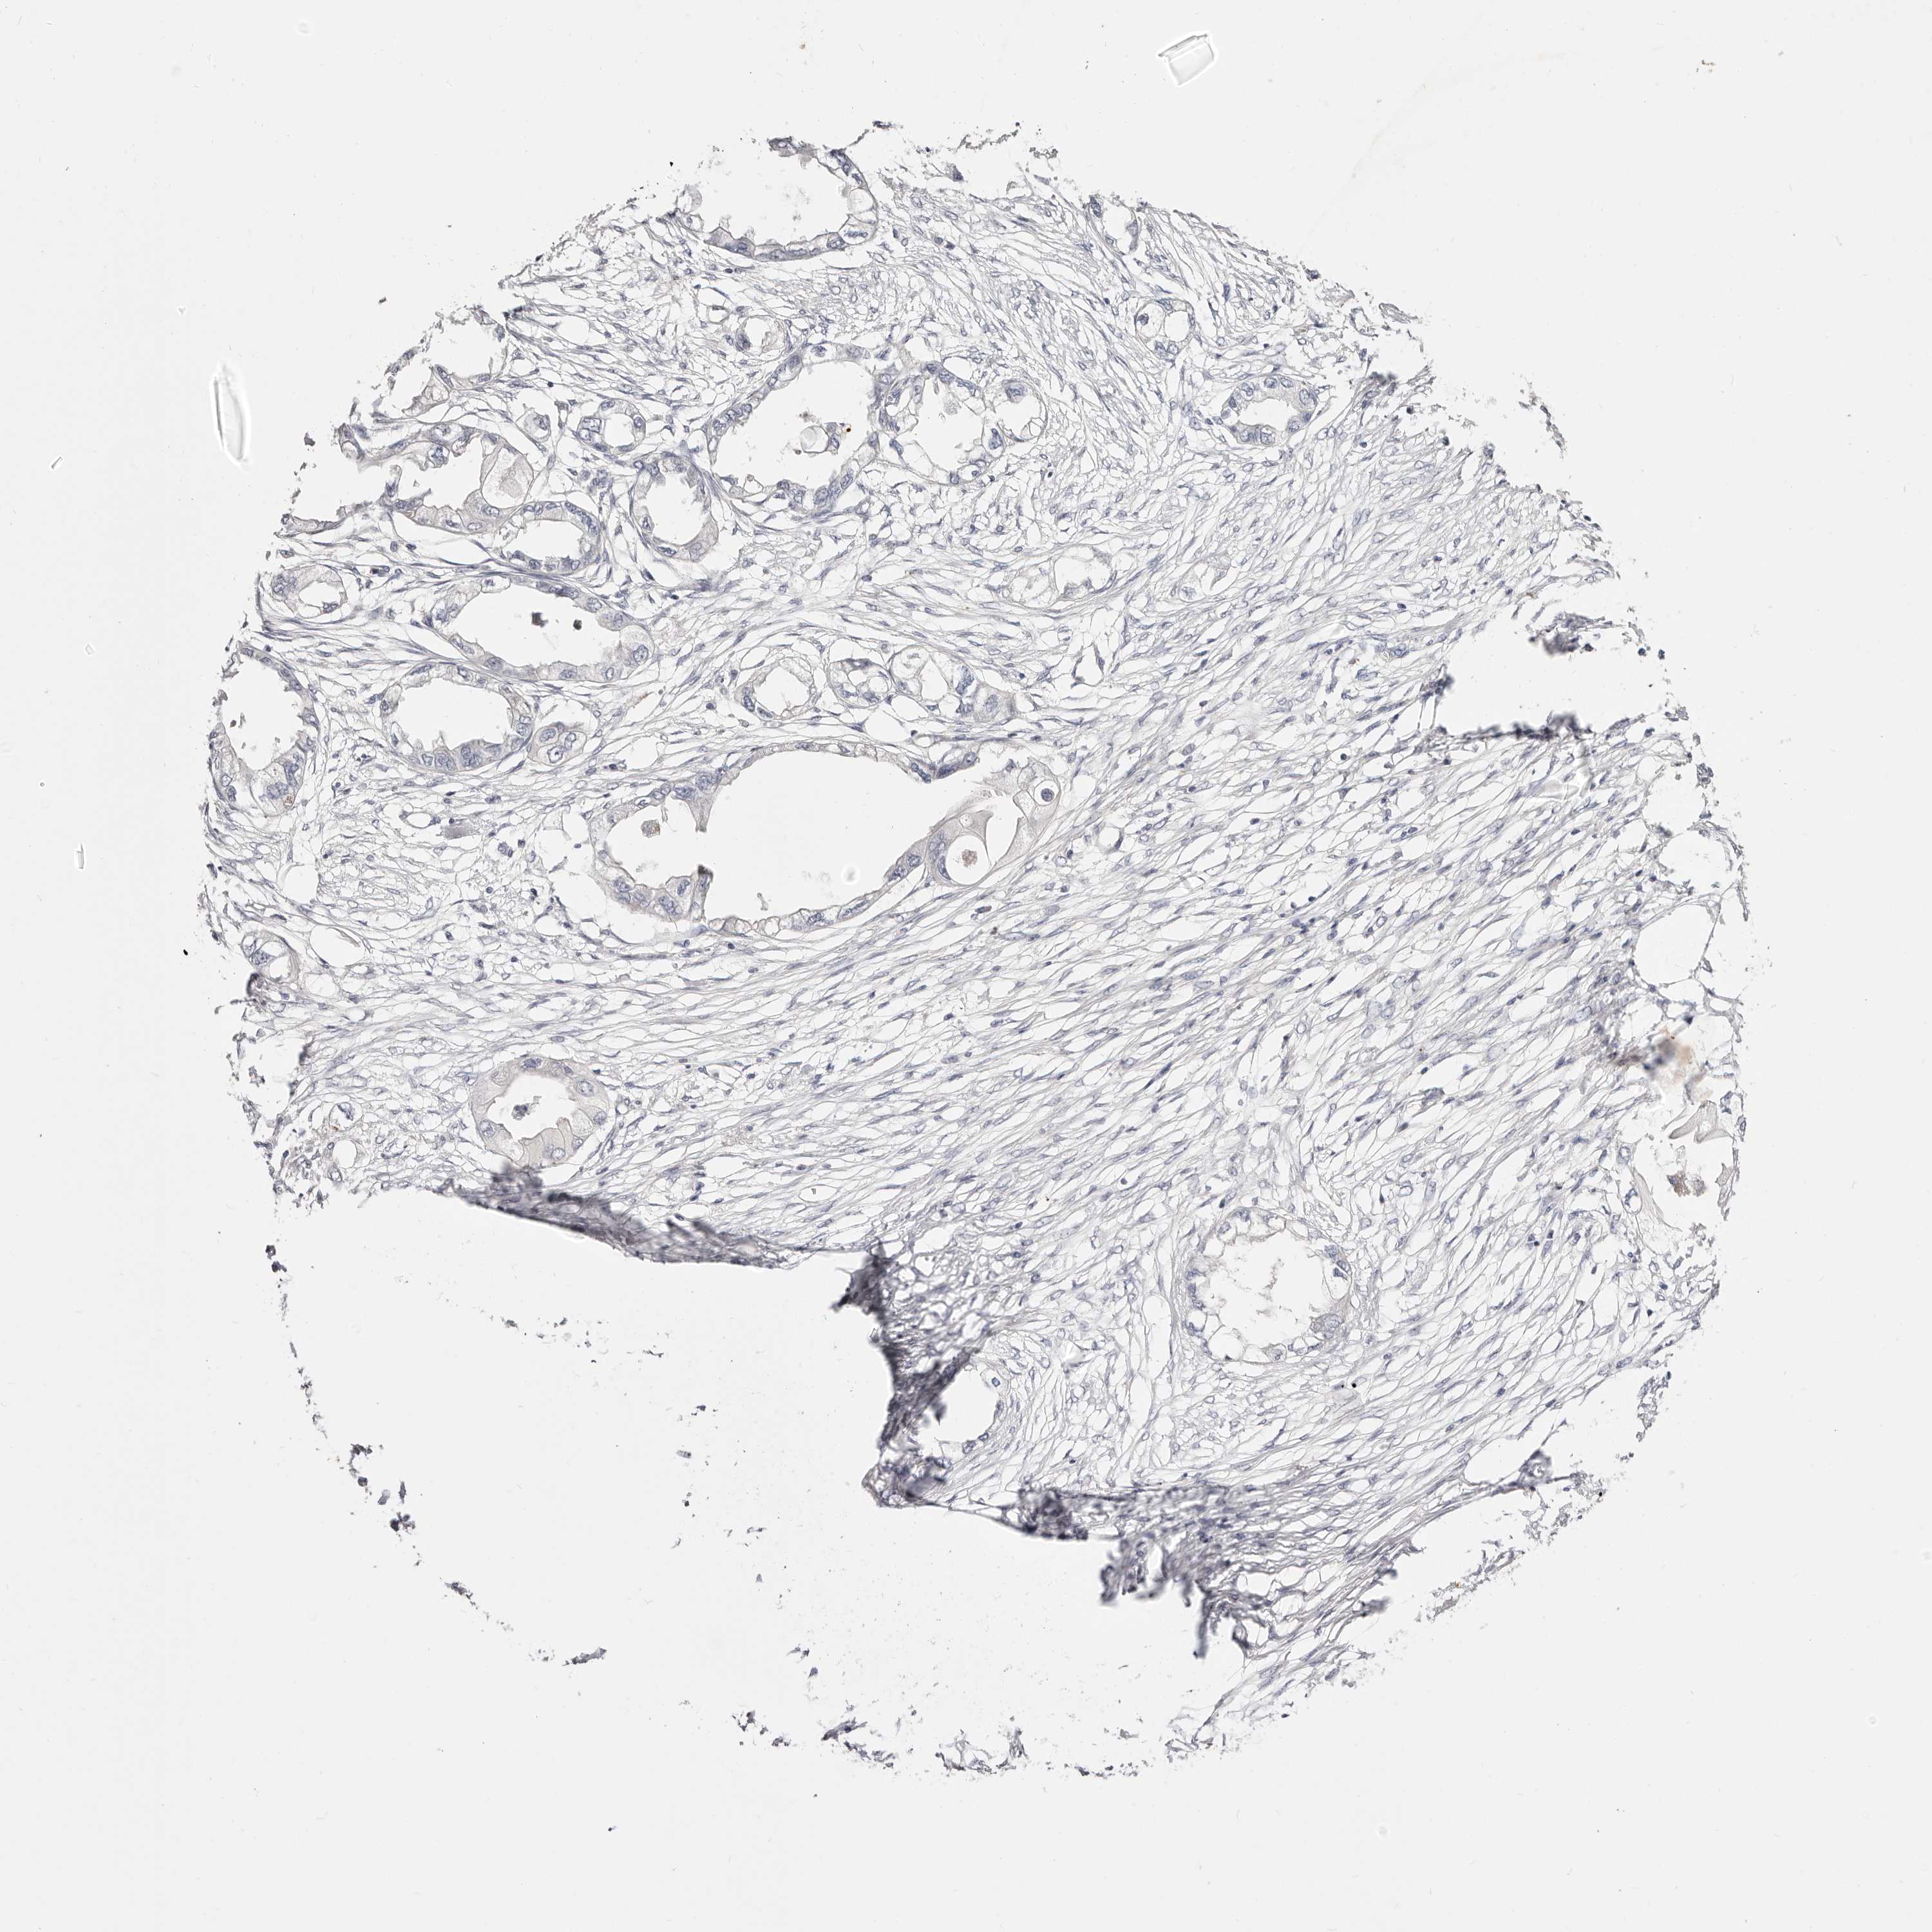

ENDOMETRIAL CANCER - Protein expressioni

A mouse-over function shows sample information and annotation data. Click on an image to view it in a full screen mode. Samples can be filtered based on level of antibody staining by selecting one or several of the following categories: high, medium, low and not detected. The assay and annotation is described here.

Note that samples used for immunohistochemistry by the Human Protein Atlas do not correspond to samples in the TCGA dataset.

Antibody stainingi

Antibody staining in the annotated cell types in the current human tissue is reported as not detected, low, medium, or high, based on conventional immunohistochemistry profiling in selected tissues. This score is based on the combination of the staining intensity and fraction of stained cells.

Each image is clickable and will lead to virtual microscopy that enables deeper exploration of all samples and also displays staining intensity scores, fraction scores and subcellular localization as well as patient and tissue information for each sample.

Antibody HPA029638

Staining

High

Medium

Low

Not detected

Intensity

Strong

Moderate

Weak

Negative

Quantity

>75%

75%-25%

<25%

None

Location

Nuclear

Cytoplasmic/membranous

Cytoplasmic/membranous,nuclear

Adenocarcinoma, NOS

Adenocarcinoma, metastatic, NOS